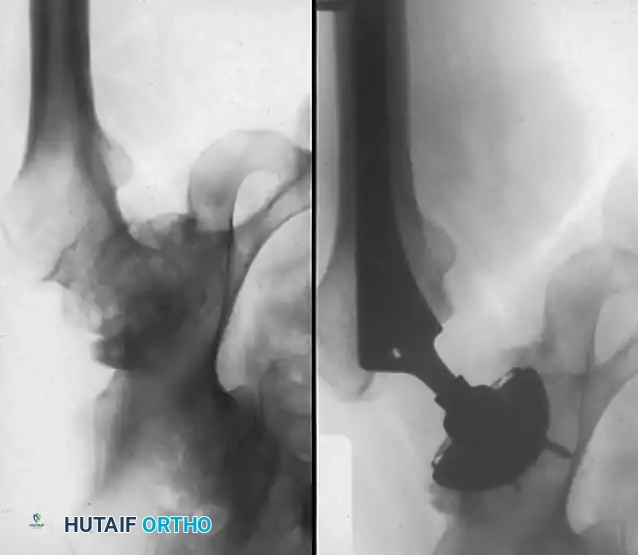

Due to the medial migration of the femur, the sciatic nerve is drawn closer to the joint than normal. It